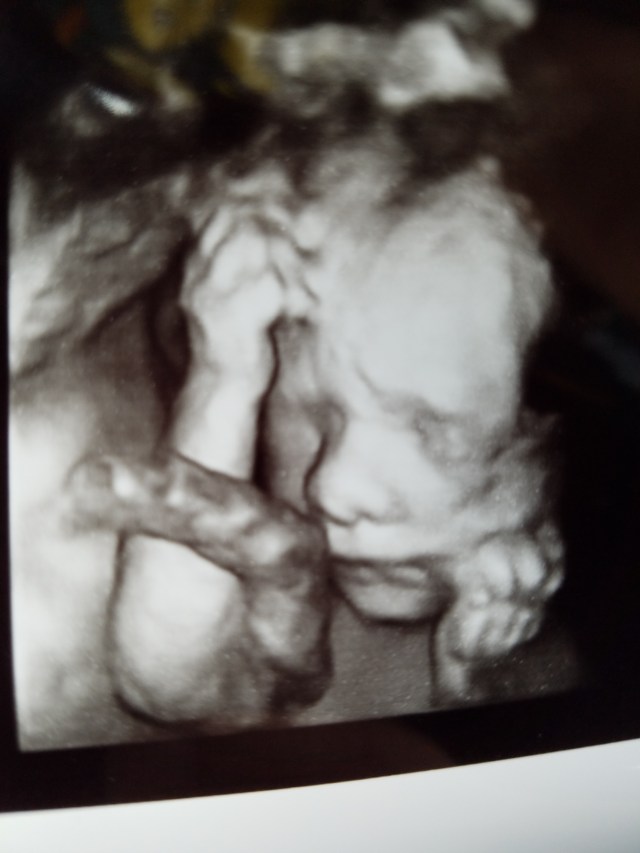

20 Weeks!